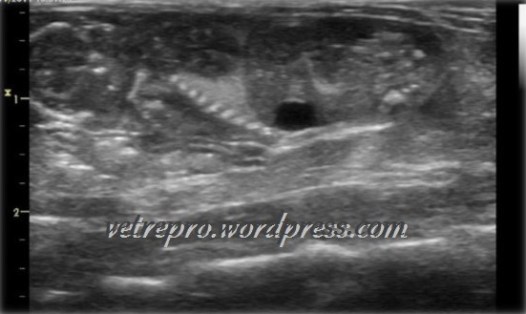

Pregnancy diagnosis of the rat at the 8th day (Image by George Mantziaras)

Heart rate estimation of a rat fetus at the 12th day of pregnancy (Image by George Mantziaras)

Ultrasound of a rat fetus on the 18th day of pregnancy (Image by George Mantziaras)